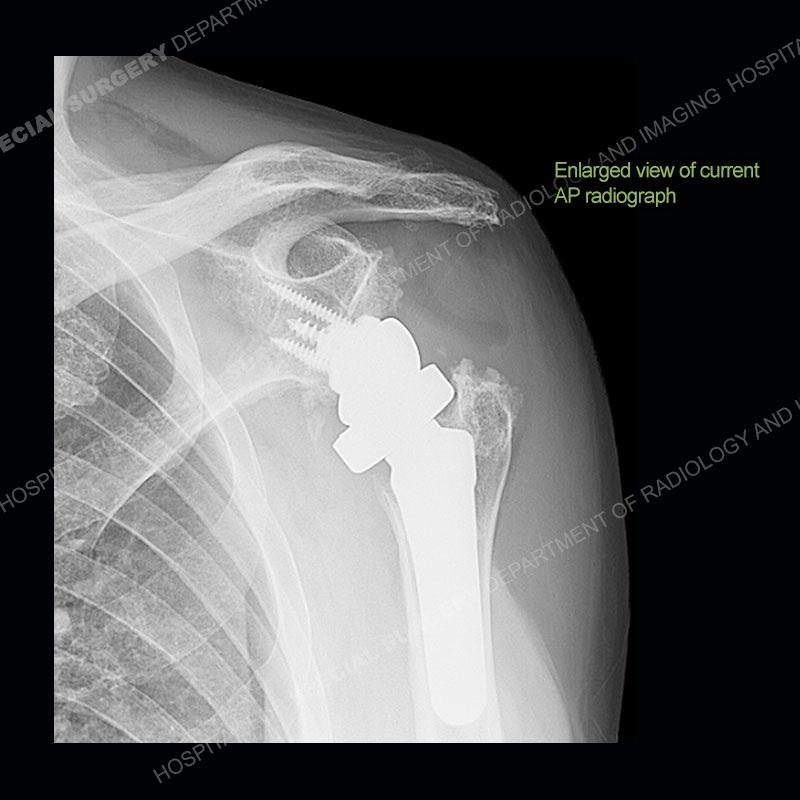

When comparing the radiographs, there is a slight change in the alignment in the components of the prosthesis. On the current radiographs, a radiolucent, crescentic focus is present at the level of the glenoid. When comparing the CT exams, there is a change at the alignment of the glenosphere and the humeral component and now a direct apposition of the components. On the current CT, the radiolucent, crescentic focus is again identified.

If comparison radiographs are present, subtle changes can be made more apparent. Instead of a space between the glenosphere and the humeral tray, there is a direct contact, and there may be an overall change in the alignment at the articulation. The displaced, radiolucent polyethylene liner depending on location can be seen on the radiographs, as in this case. At times, the liner may overlie other structures making identification very difficult on radiographs, but it should almost always be able to be identified on CT (as shown in this example as well). This patient is scheduled for revision procedure.